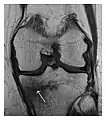

The greater tuberosity of the humerus is also an illustrative location of occult fractures. The osseous injury may follow seizures, glenohumeral dislocation, forced abduction, or direct impaction. They are commonly discovered on MRI in symptomatic patients with suspicion of rotator cuff tear. Coronal images are best suited for detection. They appear as crescentic oblique lines surrounded by a bone marrow edema pattern (Figure 5). The rotator cuff must be inspected since associated ligamentous lesions are common. In the ankle, malleoli and tarsal bones should be checked carefully for any cortical disruptions and radiolucent lines that may reveal a fracture. Awareness of the exact location of the pain will help direct the attention of the interpreter when searching for very subtle signs of fracture (Figure 6).[1]

a

b

Figure 7: Fatigue fracture of the talus in a 25-year-old male basketball player with right hind foot and ankle pain, without history of trauma, and a normal initial radiograph (not shown). (a) One-month followup lateral radiograph shows normal appearance. (b) Sagittal T1-weighted MRI shows an irregular fracture line (arrow) within an ill-defined area of hypointensity corresponding to bone marrow edema.[1]